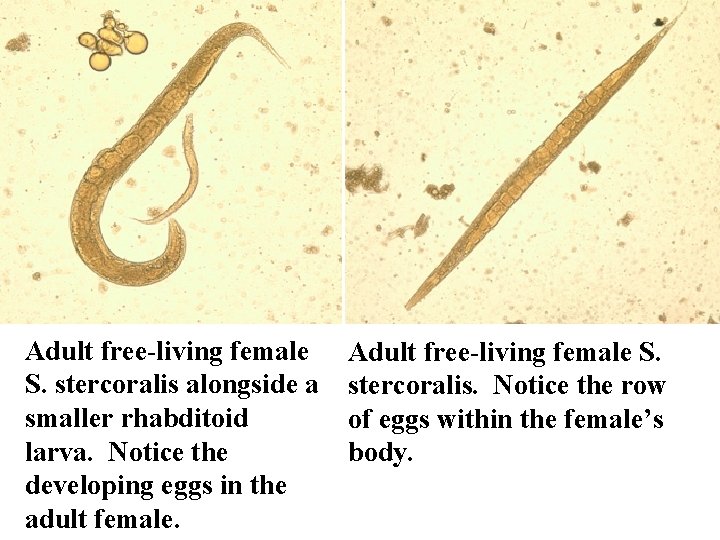

Adult free-living female S. stercoralis alongside a smaller rhabditoid larva. Notice the developing eggs in the adult female. Adult free-living female S. stercoralis. Notice the row of eggs within the female’s body.